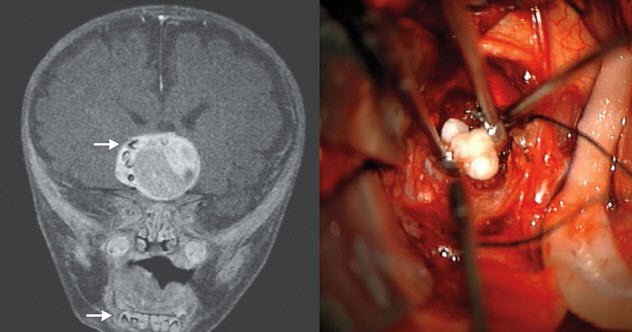

Một em bé bốn tháng tuổi được chẩn đoán mắc một khối u não hiếm gặp. Lúc đầu các bác sĩ đã hết sức lo lắng khi đầu của em to nhanh hơn bình thường, và các xét nghiệm chiếu chụp đã kết luận rằng có một khối u trong não của em. Nhưng điều kỳ lạ là các hình ảnh cũng cho thấy một thứ gì đó khác - một thứ gì đó nhỏ, xương và rắn, rất kỳ quặc. Sau khi được lấy ra trong quá trình phẫu thuật, khối u đã tiết lộ thứ chứa bên trong nó - một cái răng đã phát triển đầy đủ!

Điều kỳ lạ không kém là tình trạng này cũng có một cái tên: craniopharyngioma (u sọ hầu). Tuy nhiên, đây là lần đầu tiên người ta thực sự tìm thấy một cái răng trong khối u loại này.